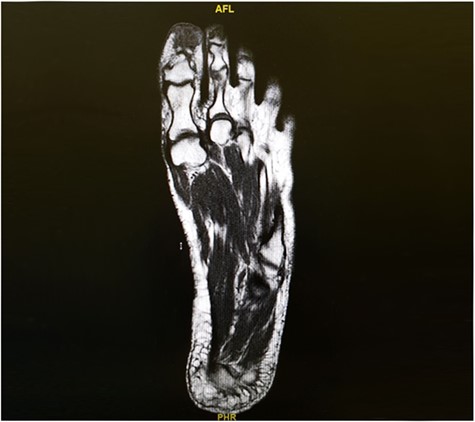

MRI showed a 2-cm soft tissue focus at the tip and plantar aspect of big toe closely adherent to the tuft of distal phalanx but with no evidence of bony destruction (Fig. 2).

Pre-excision MRI for the right foot showing a 2-cm soft tissue focus at the tip and plantar aspect of big toe closely adherent to the tuft of distal phalanx but with no evidence of bony destruction.